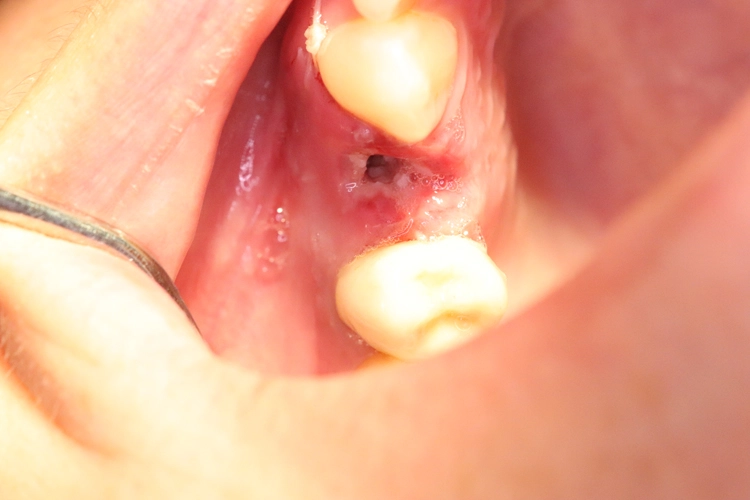

Aufgrund der traumatischen Extraktion des ankylosierten Zahnes, die zu einer Osteotomie wurde (Abb. 3), fehlten die vestibuläre und palatinale Lamelle (Röntgenkontrollbild während der Osteotomie, Wurzelrest noch vorhanden Abb. 4). Dieser Wurzelrest wurde entfernt. Bei dem geringen Restknochenvolumen war eine Sofortimplantation nicht mehr indiziert.